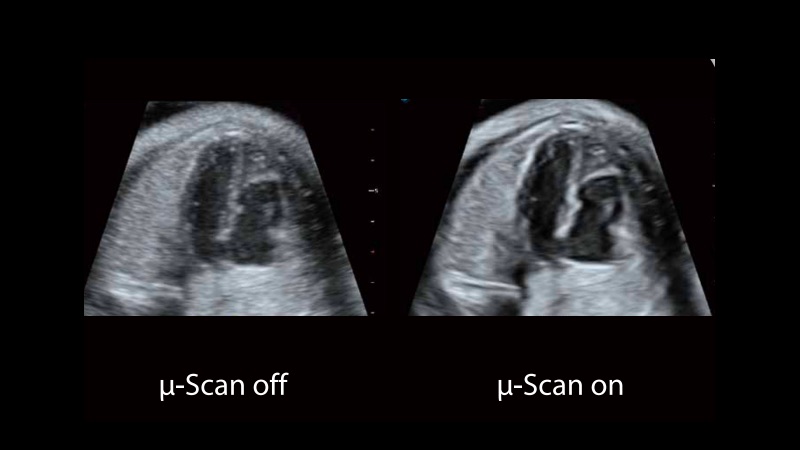

新一代微米成像技術(shù)大大提高了器官和病變的可見性。高清對(duì)比度分辨率將抑制斑點(diǎn)噪聲,同時(shí)保持真實(shí)的組織結(jié)構(gòu)。